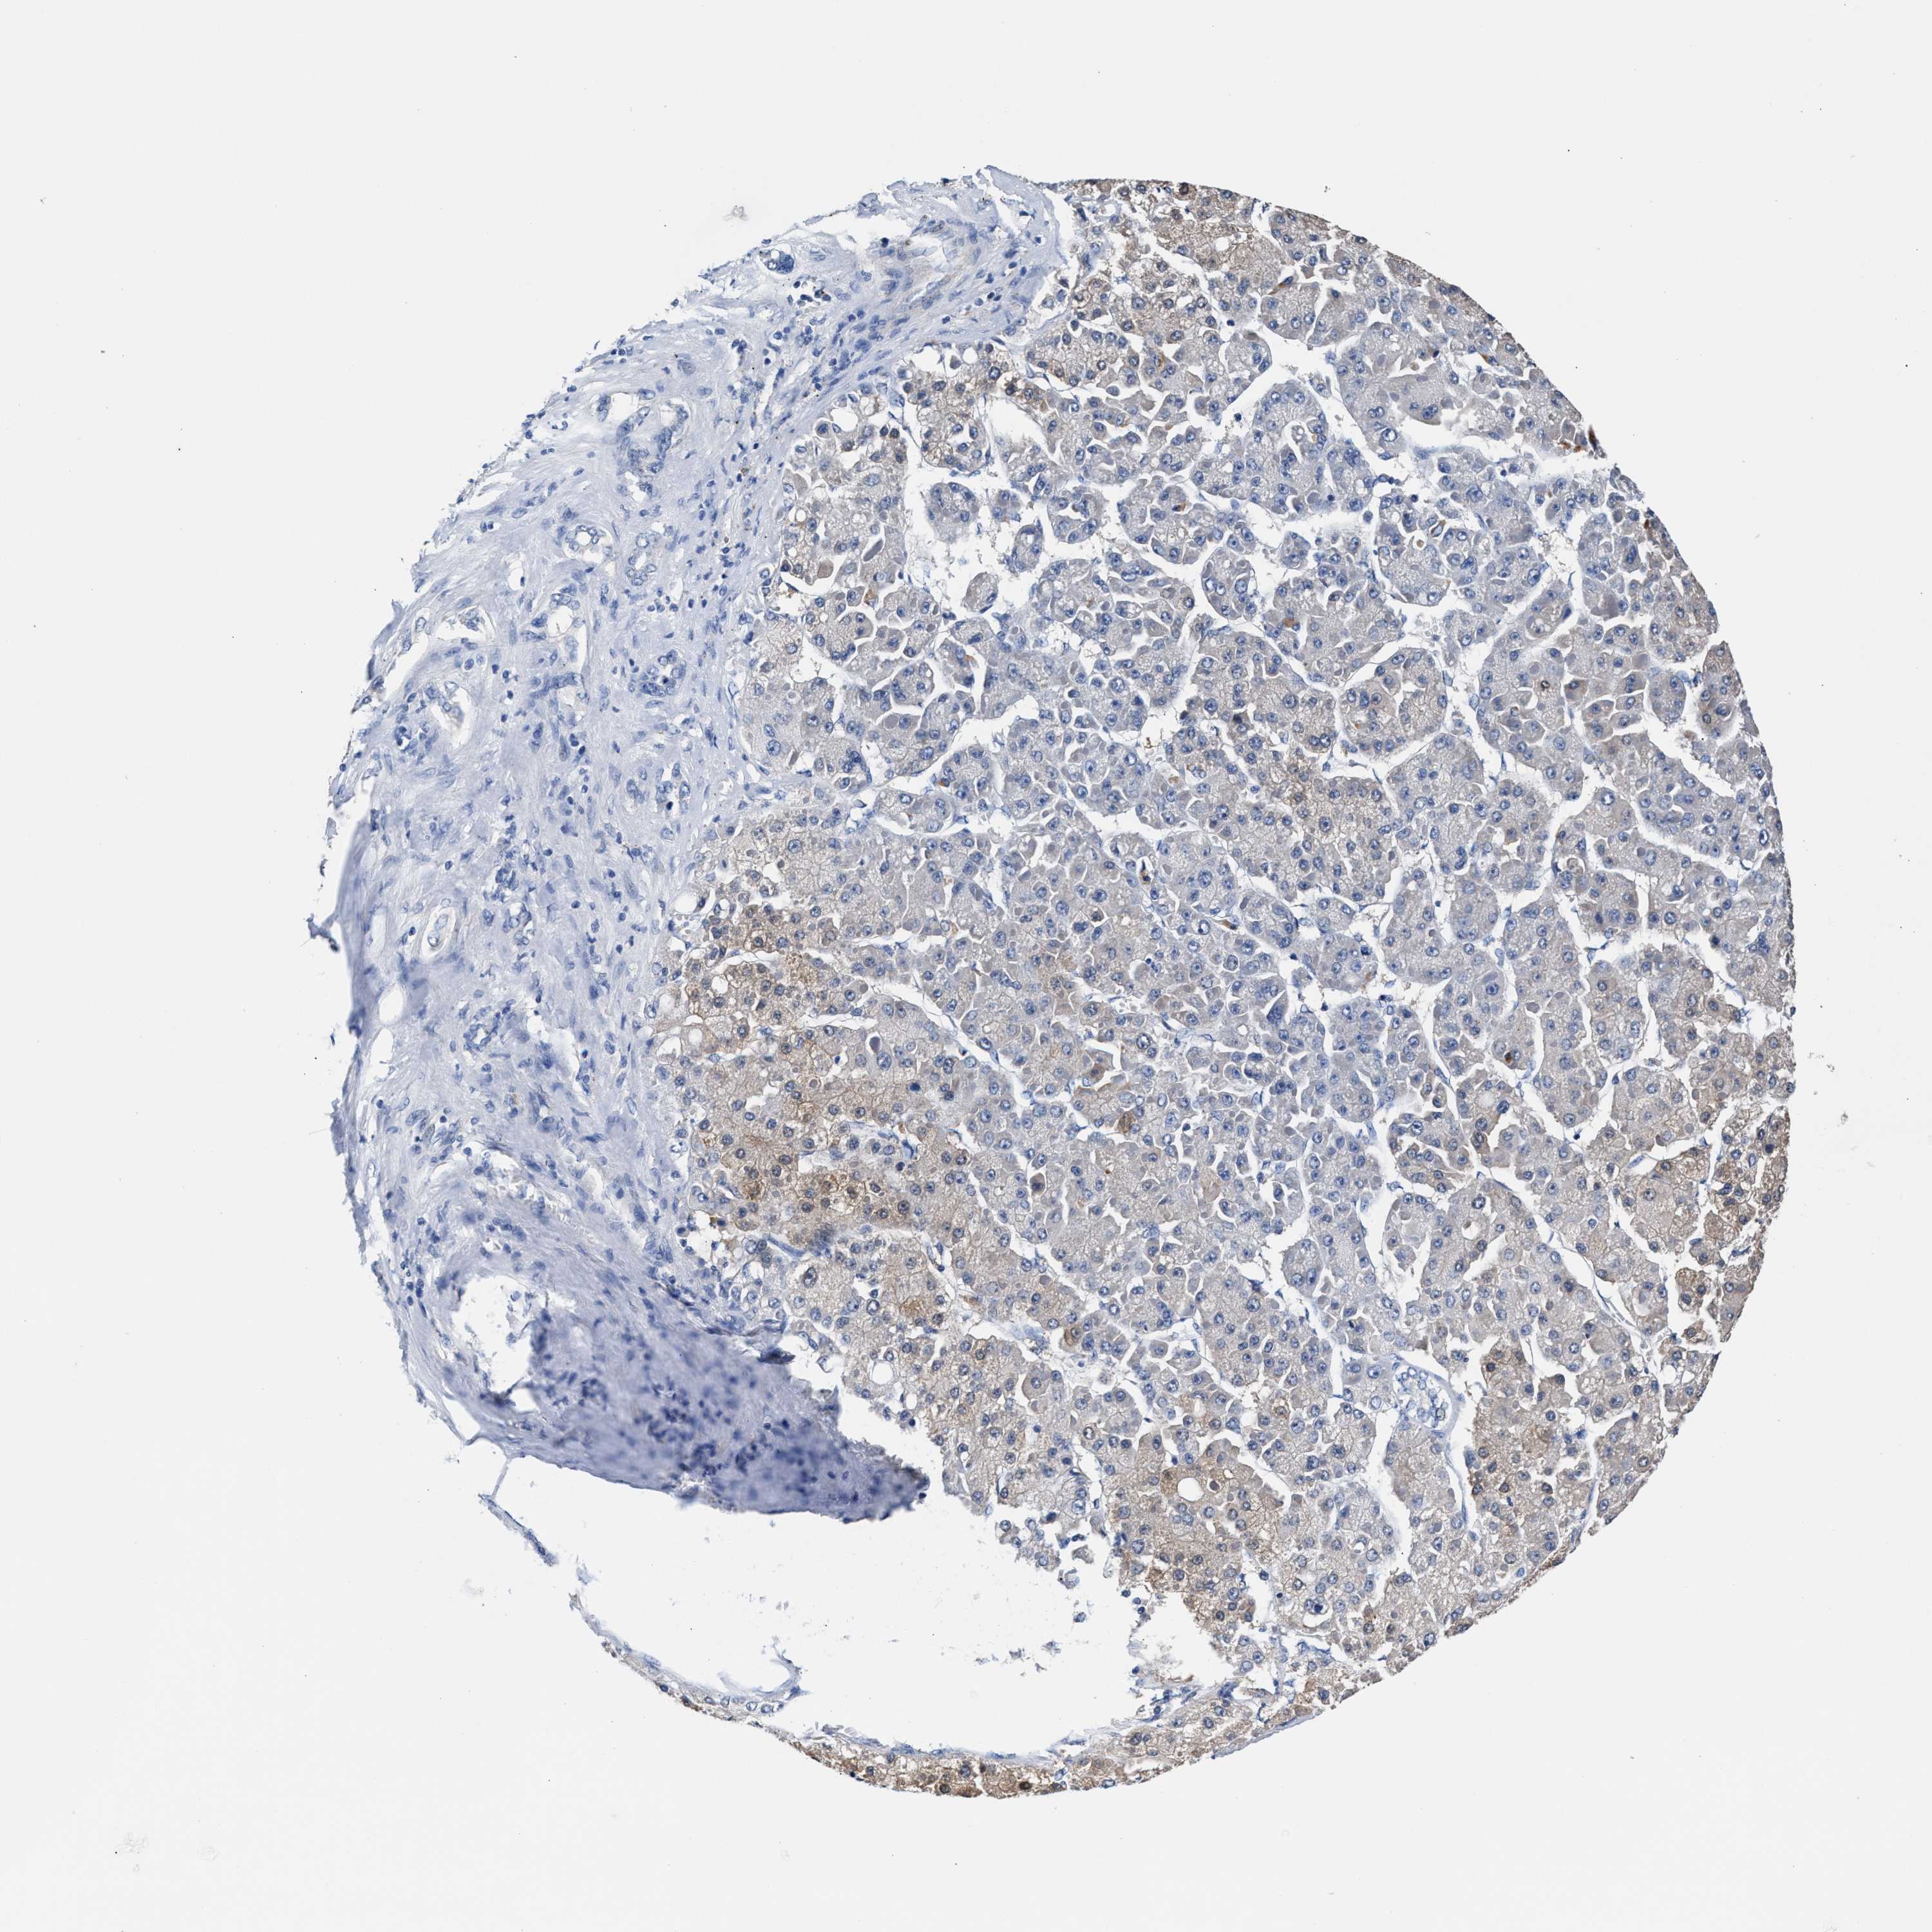

LIVER CANCER - Protein expressioni

A mouse-over function shows sample information and annotation data. Click on an image to view it in a full screen mode. Samples can be filtered based on level of antibody staining by selecting one or several of the following categories: high, medium, low and not detected. The assay and annotation is described here.

Note that samples used for immunohistochemistry by the Human Protein Atlas do not correspond to samples in the TCGA dataset.

Antibody stainingi

Antibody staining in the annotated cell types in the current human tissue is reported as not detected, low, medium, or high, based on conventional immunohistochemistry profiling in selected tissues. This score is based on the combination of the staining intensity and fraction of stained cells.

Each image is clickable and will lead to virtual microscopy that enables deeper exploration of all samples and also displays staining intensity scores, fraction scores and subcellular localization as well as patient and tissue information for each sample.

HPA048652

HPA055972

HPA055973

CAB022669

CAB047357

Cholangiocarcinoma

Carcinoma, Hepatocellular, NOS